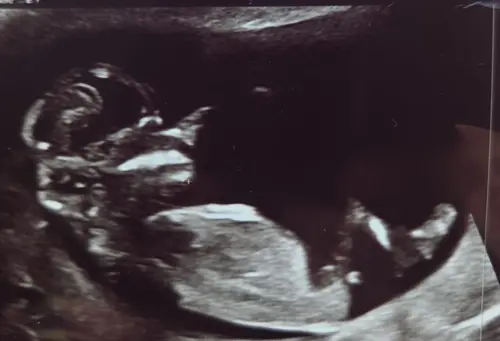

Ik denk meisje. Bij jongen zou het volgens mij echt meer naar boven moeten steken.

Jaaa ik raak zoo zenuwachtig hahaha maar dat heb je met die theorie毛n natuurlijk. Ik zie zelf idd ook meisjes nub

Het geslacht is niet helemaal duidelijk te zien, dus het zou zo goed een meisje als jongen kunnen zijn. Maar ik gok een meisje! 馃

Is dat uitsteeksel dAn niet de nub? Dacht ik haha馃き

Hahah dat zou je zeggen he maar het is een beetje een onduidelijke positie waarbij het niet goed te zien is

Jaa dat zei de verloskundige idd maar ik denk idd dan veen ervoor. Heb 1 waar je hem helemaal ziet. Theorie毛n blijven lastig 馃き馃槀